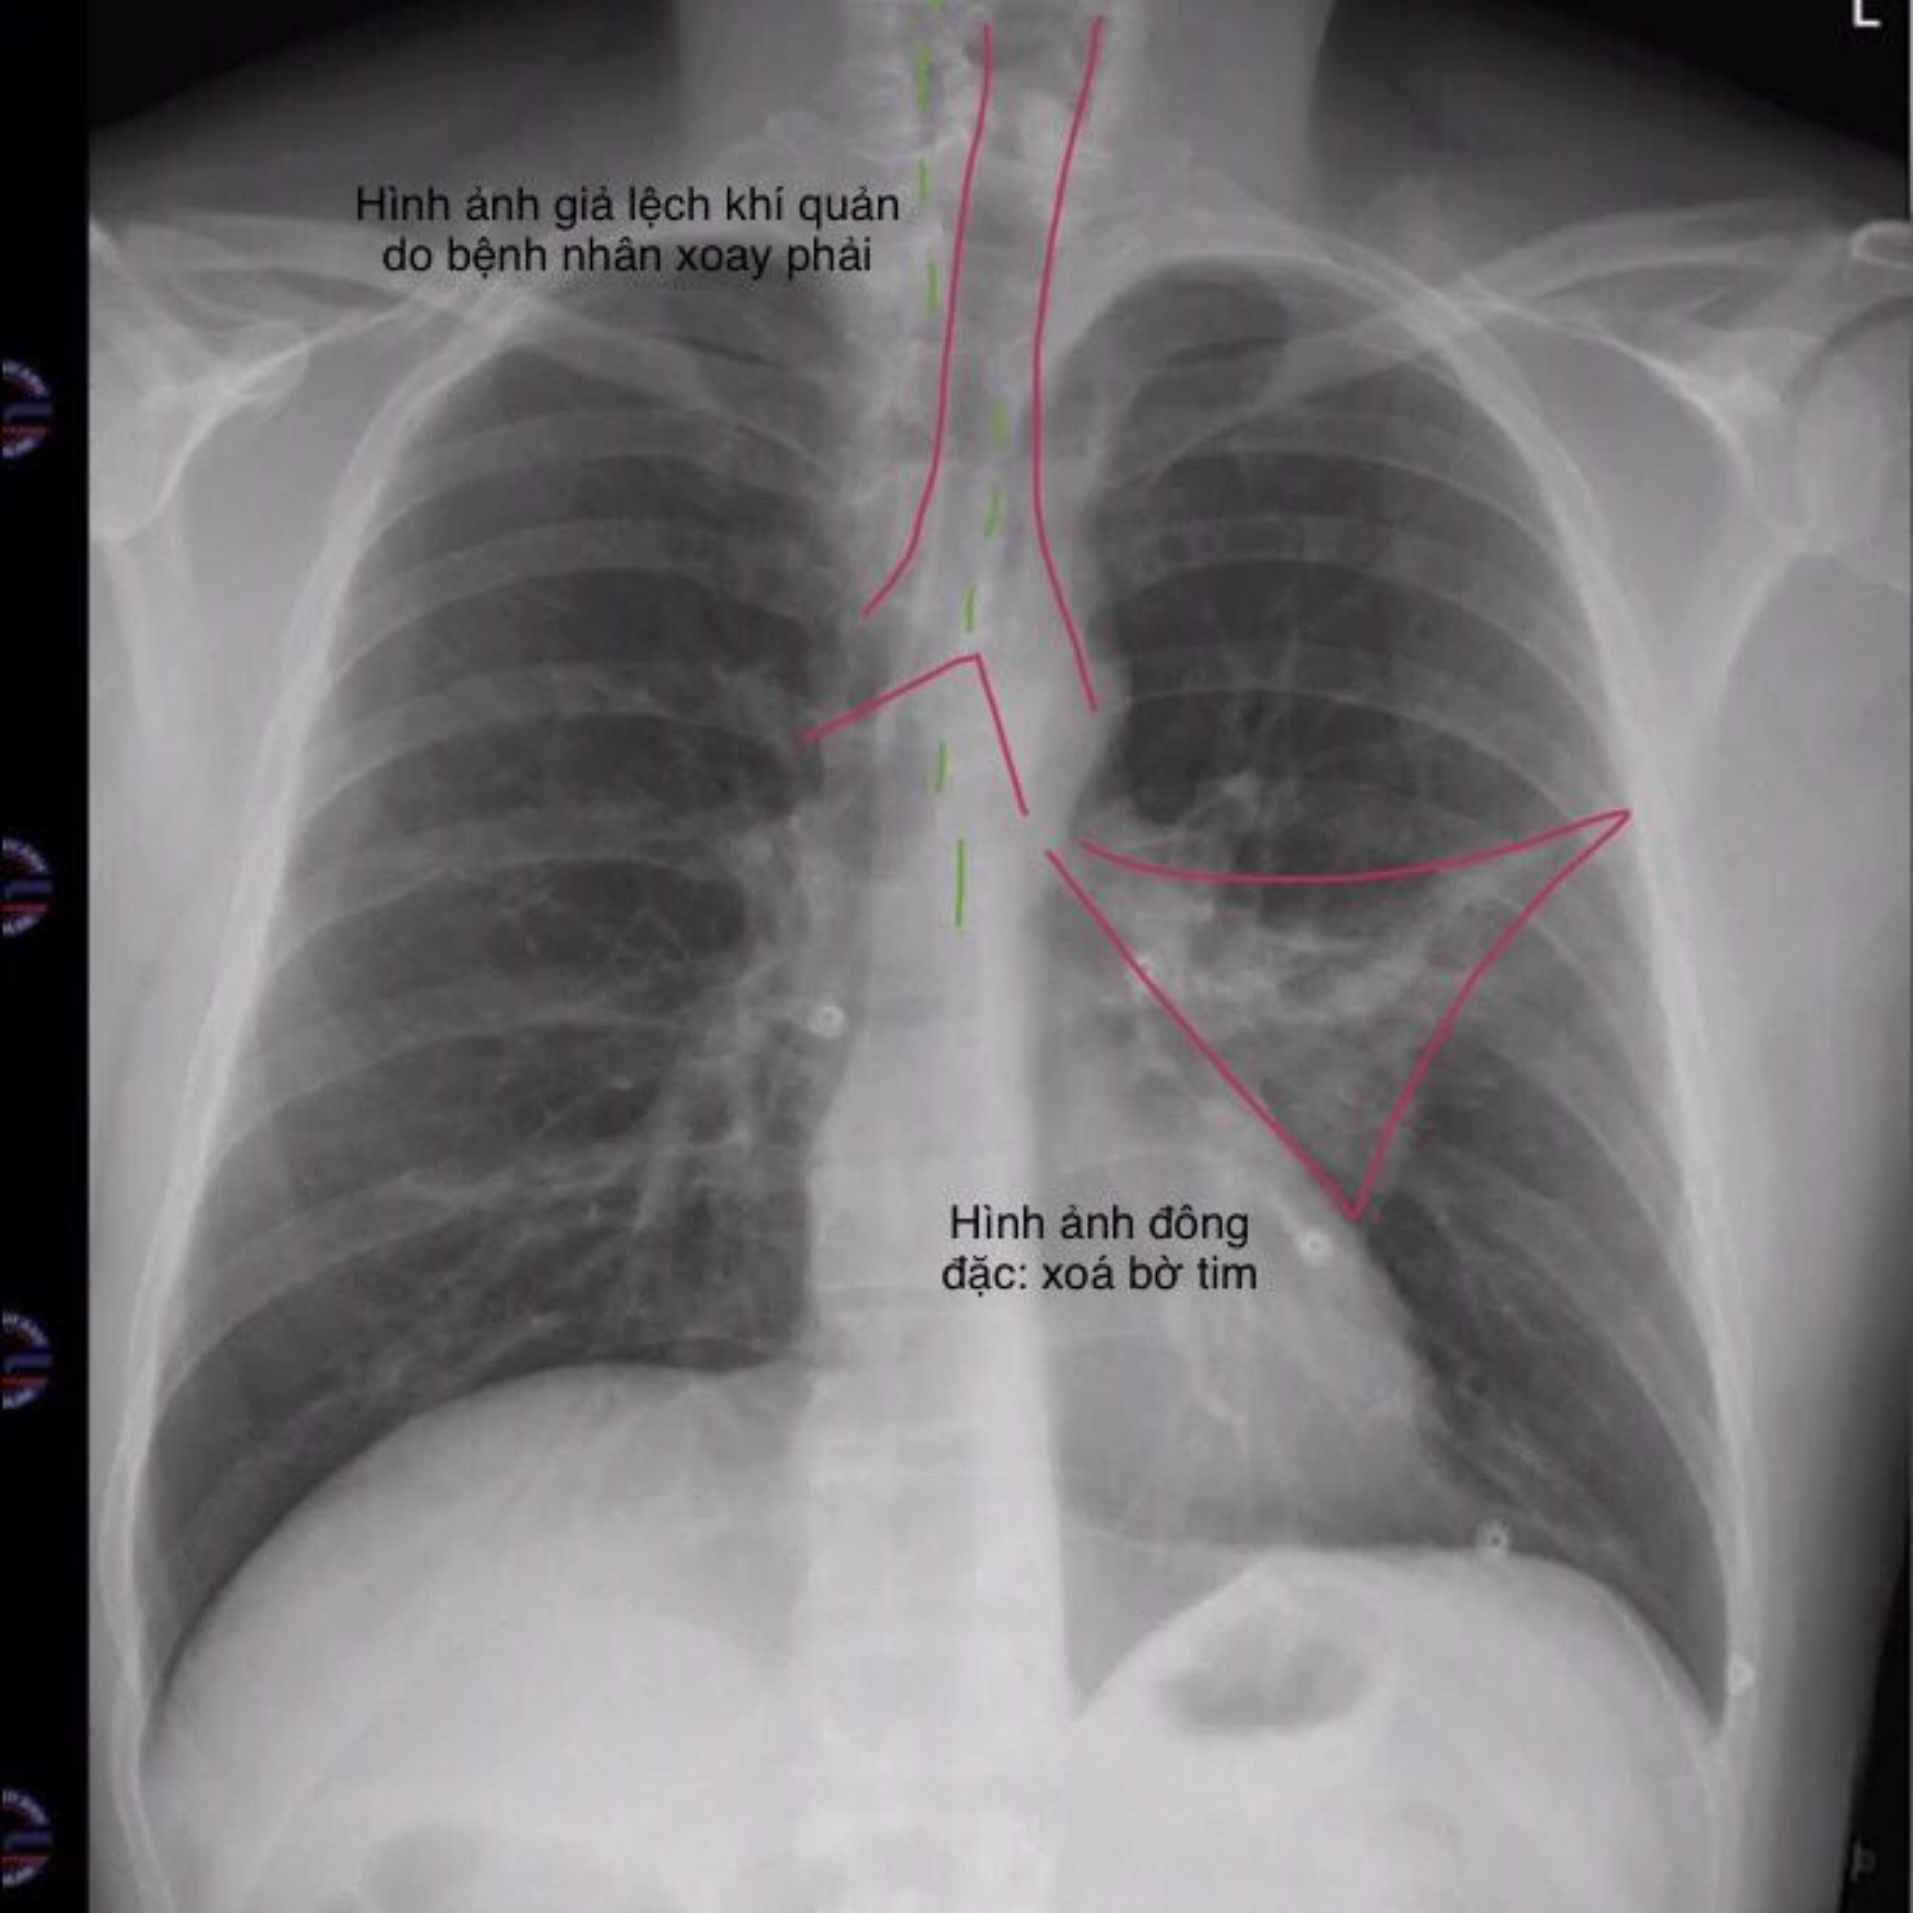

Tâm nhĩ trái (Left Atrium): Nằm phía sau tim, không tạo bờ rõ trên phim X-quang ngực thẳng. Tuy nhiên, khi tâm nhĩ trái lớn, nó có thể đẩy khí quản lệch phải hoặc chèn ép thực quản, là một dấu hiệu quan trọng trong giải phẫu trên X-quang ngực thẳng.